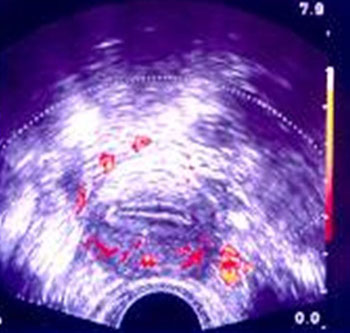

Εικόνα 3. Προωοθυλακιορρηκτικό

Doppler μητριαίας αρτηρίας: το διαστολικό κύμα καλύπτει ολόκληρη τη διαστολική

φάση χωρίς εγκοπή.